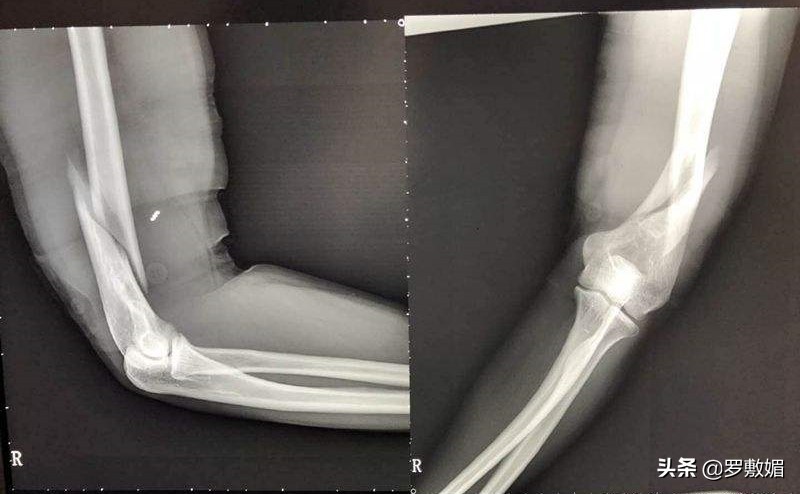

班主任二话不说,立即开车把邵某轩送回家,邵某轩的父母见病情严重,和班主任一起送到了东营市人民医院急救室。经CT扫描检查,邵某轩被确诊为左臂肱骨粉碎性骨折。

肱骨骨折图